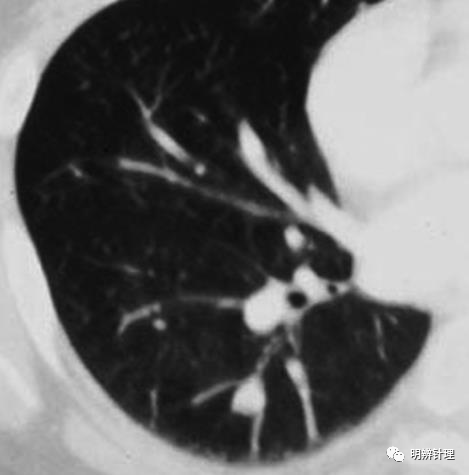

右肺下叶基底段见10mm实性结节,完全符合良性特征的老实结节,偏要欺负身旁,挤压局部支气管和血管。

诊断结果:类癌